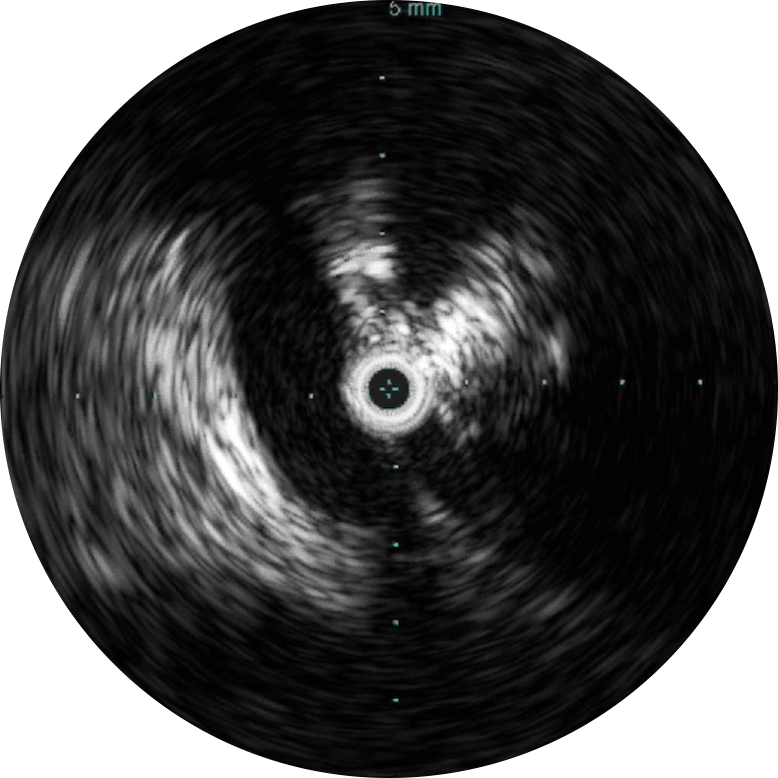

Визуализация на 360 ̊ способствует лучшему пониманию заболевания и придаточных структур, к которым также относятся уровень компрессии, остеофиты, тромбы и прочее.

Цифровой катетер для ВСУЗИ Visions PV (0,035 дюйма) дополняет стандартные инструменты проведения ангиографических процедур, обеспечивая оценку морфологии кровеносных сосудов и их визуализацию в поперечном сечении. Благодаря рабочей длине, равной 90 см, и максимальному диаметру визуализации, равному 60 мм, для инвазивных процедур с использованием проводника диаметром 0,035 дюйма, устройство облегчает диагностику заболеваний вен и периферических артерий и помогает врачам выбрать правильный подход к лечению с учетом индивидуальных потребностей пациента.